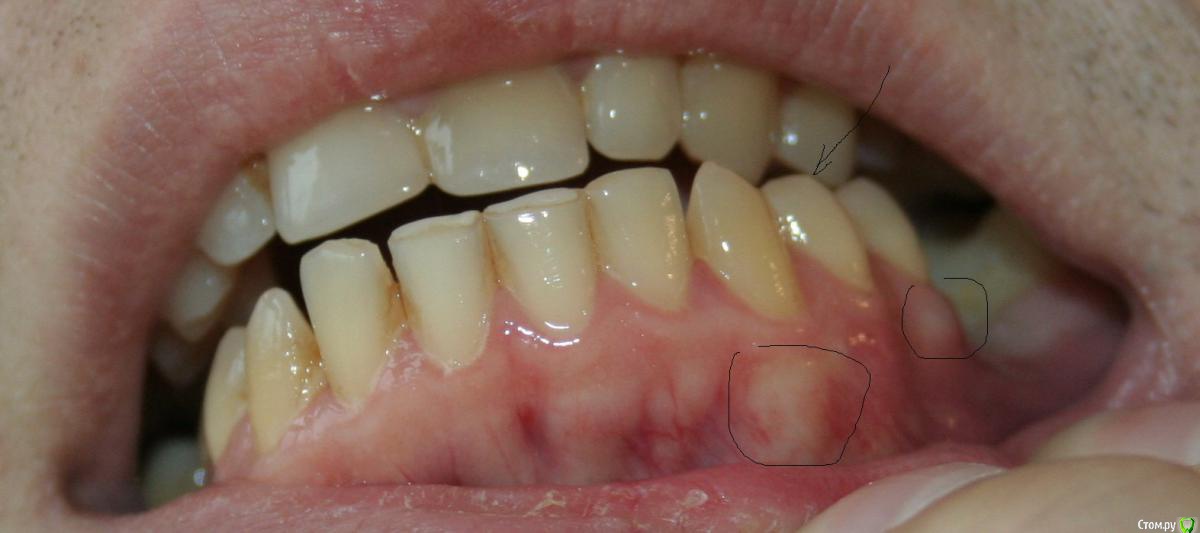

Xael Опубликовано 7 ноября, 2017 Автор Поделиться Опубликовано 7 ноября, 2017 (изменено) Добавляю рентген-фото больного зуба 3.4: Добавляю также фото больной(?) десны: Изменено 7 ноября, 2017 пользователем Xael Ссылка на комментарий

Xael Опубликовано 6 ноября, 2017 Поделиться Опубликовано 6 ноября, 2017 (изменено) Здравствуйте, уважаемые врачи и просто читатели этого замечательного (безо всякого сарказма) форума! У меня, как неожиданно выяснилось, уже несколько лет бруксизм, сильная стираемость зубов А 2 недели назад болезнь, внезапно, вообще, нанесла непоправимый и катастрофический урон моим зубам (С проблемами большинства пострадавших зубов удалось как-то, худо-бедно, но справиться, но вот один... так и не могу вылечить, местные врачи разводят руками. 1. начал он болеть после особо сильного приступа бруксизма (днем был большой стресс, затем сильно сжал и тер зубы во сне)2. на 4 зубах, включая и этот, сбоку появились вертикальные трещины, еще один стал болеть от стертости (прошел за пару дней после Фторлака), на еще одном выкрошилась пломба (починили уже)3. визуально: жеват. поверхность коронки зуба не расколота, трещина выглядит неглубокой и не уходит под десну, но сама десна покрасневшая, под двумя соседними зубами она теперь постоянно содержит какие-то белесые пятна, но именно классич. свища и гноетечения не видно нигде4. на рентгене ничего криминального (смотрели разные врачи), да и рано еще для изменений в кости5. болит явно больше вечером6. всегда болит при накусывании, шевелении его языком и т.д. (движение зуба из стороны в сторону)7. если сильно разболелся, то болит постоянно, любое, даже самое нежнейшее, прикосновение резко усиливает боль8. если сильно разболелся, то реагирует даже на изменение температуры окружающей среды (улица- помещение)9. постоянная боль ощущается как очень сильное онемение, с толикой жжения, зуб "горячий", иногда боль отдает в зубы над ним, но в глаза, шею или уши не иррадирует, никогда10. если его СОВСЕМ не трогать (это чрезвычайно сложно) в течение 4-5 часов, то он может постепенно совсем перестать болеть, чувствительность к любым раздражителям почти полностью пропадает, но жевать на нем все равно нельзя, опять заболит11. очень редко его дергает, как от нарыва12. соседние с ним зубы тоже болели, похожим образом, но гораздо слабее и давно перестали13. никогда не болит от постукиваний по нему инструментом стоматолога 14. если разболелся, иногда удается успокоить очень холодным компрессом15. всегда частично помогает стомат.гель Холисал (странно, ведь он действует только на десну, по идее)16. всегда помогает препарат Кетанов (но его нельзя пить каждый день, увы)17. Фторлак не помогает совсем18. на горячее не реагирует, на холодное есть некоторая реакция19. болит уже 2 недели и не ослабевает, иногда уровень боли достигает пульпитного, почти ничего не ем и плохо сплю, т.ч. плиз ХЕЛП! П.С. знаю, по правилам форума, нужно разместить рентген-фото, но в моем случае оно не имеет особого смысла, т.к., как мне объяснили, так быстро изменения в костн. ткани не произойдут. Изменено 6 ноября, 2017 пользователем Xael Ссылка на комментарий